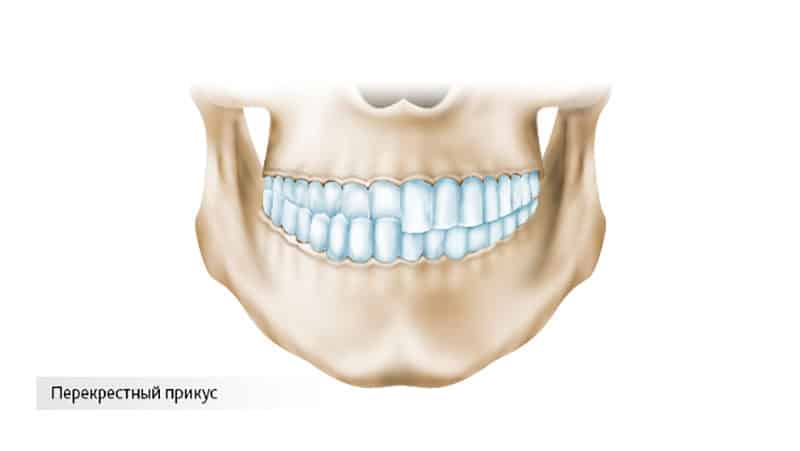

Перекрестный прикус — стоматологическая аномалия, возникающая у детей и взрослых, характеризующаяся неправильным смыканием зубов. Это может привести к проблемам с жеванием, речью и эстетикой лица. В статье рассмотрим основные особенности перекрестного прикуса, его последствия и методы лечения для разных возрастных групп. Понимание проблемы и способов коррекции поможет читателям обратиться за помощью к специалистам и избежать осложнений.

Данная аномалия может возникать как в боковых участках челюсти, так и в её передней части. Ортодонтия выделяет несколько различных форм этой патологии:

- Буккальный прикус. При этом типе нарушается контакт боковых зубов, что затрудняет процесс жевания. В некоторых случаях челюсть может смещаться, но иногда она остаётся на своём месте.

- Лингвальный прикус. Этот тип характеризуется отсутствием контакта между антагонистами или смыканием боковых зубов, что может быть вызвано сужением или расширением верхнего зубного ряда. Такой прикус может наблюдаться как с одной стороны, так и с обеих.

- Буккально-лингвальный прикус. Он делится на три подтипа: гнатический прикус (при сужении или расширении челюстного базиса), зубоальвеолярный прикус (при недостаточном или чрезмерном развитии зубоальвеолярных дуг) и суставный прикус (сопровождающийся смещением нижней челюсти в сторону).